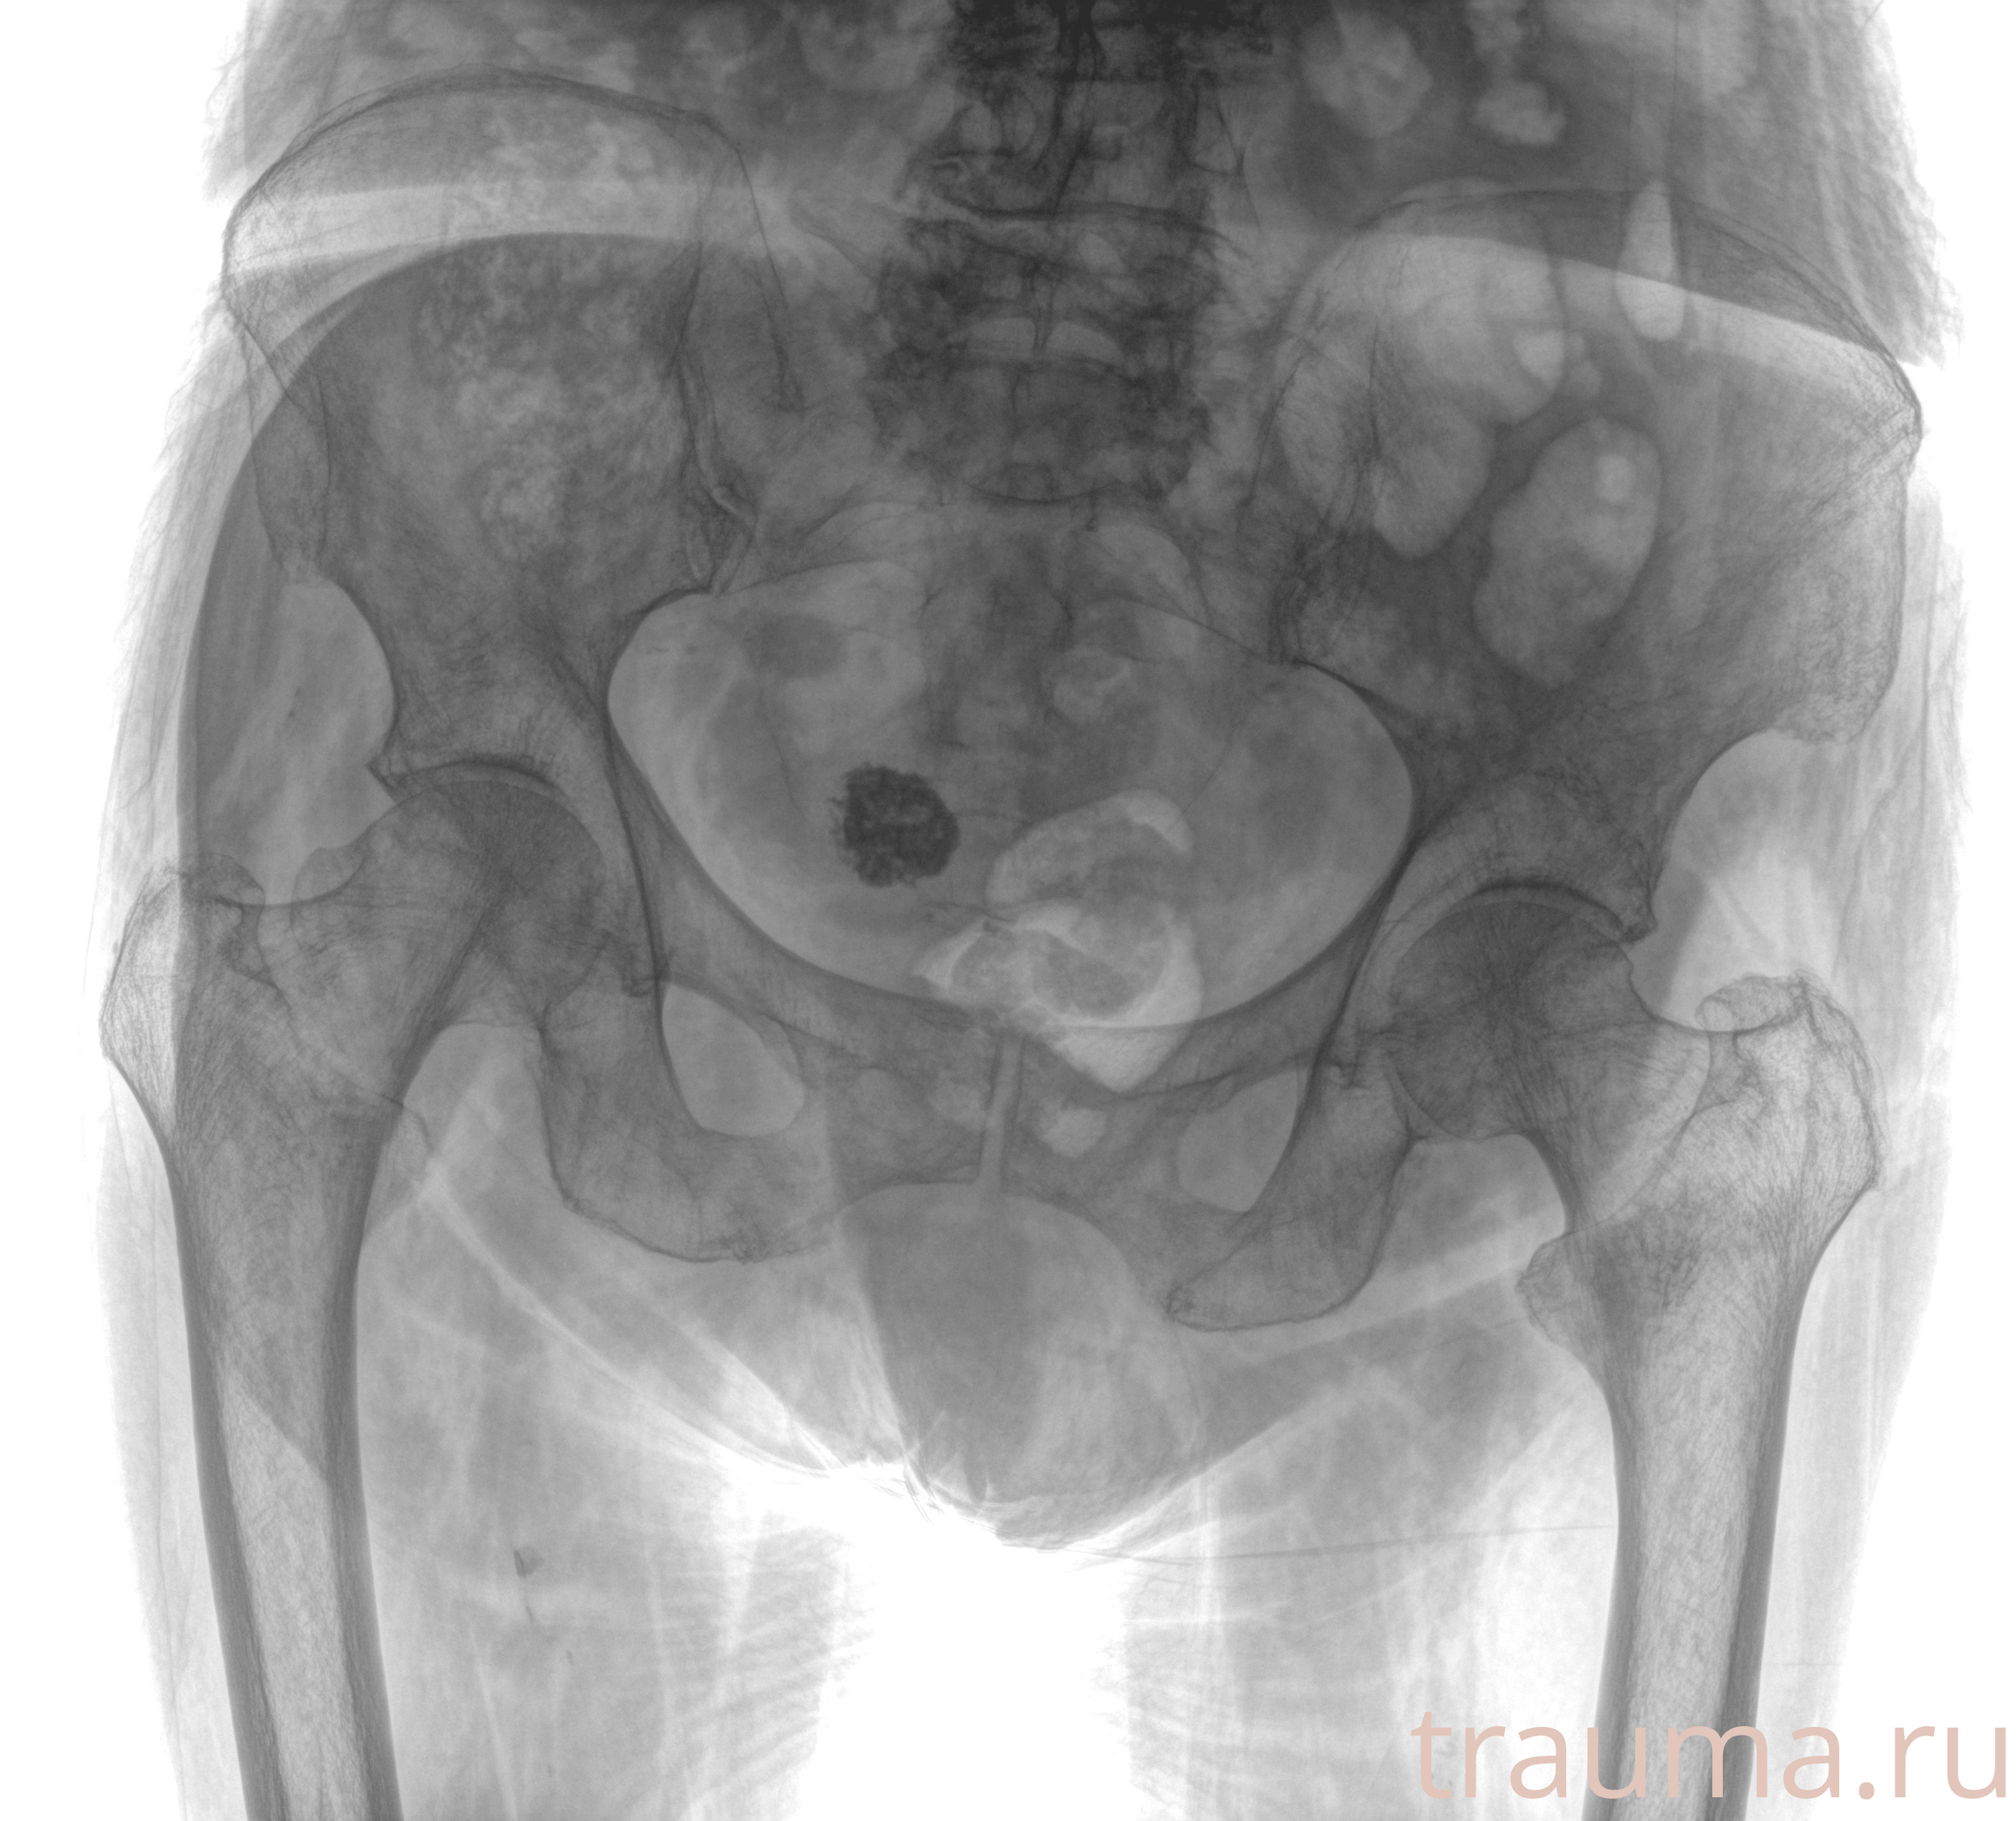

Рентгенограммы

Рентген на дому: по вашему адресу приезжает врач-рентгенолог, травматолог-ортопед с мобильным рентгеновским аппаратом, проводит диагностику травмы или заболевания, делает необходимые рентгенограммы, дает рекомендации по дальнейшему лечению. Получить качественные снимки в домашних условиях возможно благодаря уникальной методике, разработанной МосРентген Центром для института  Склифосовского